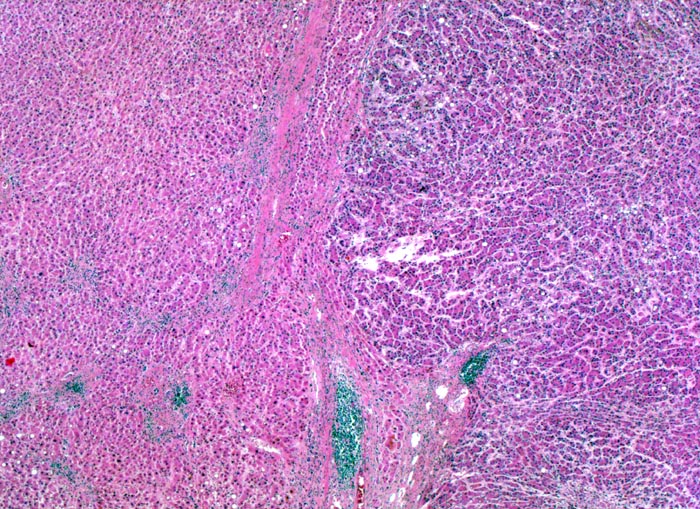

PathoPic – image database / PathoPic ID 4399 - hepatozelluläres Karzinom bei chronischer Hepatitis C

hepatozelluläres Karzinom bei chronischer Hepatitis C

Das Leberparenchym links im Bild zeigt entzündlich infiltrierte und fibrosierte Portalfelder als Folge der chronischen Hepatitis C. Der scharf begrenzte, unbekapselte Tumor rechts im Bild ist aufgrund der höheren Kern-Zytoplasmarelation mit erhöhter Zelldichte dunkler gefärbt. Innerhalb des Tumors fehlen Portalfelder. Die Tumorzellen bilden schmale Trabekel.

Patient mit bekannter chronischer Hepatitis C. Bei einer sonographischen Kontrolluntersuchung wird ein 1cm grosser Knoten entdeckt. Das Alpha-Fetoprotein im Serum ist nicht erhöht.